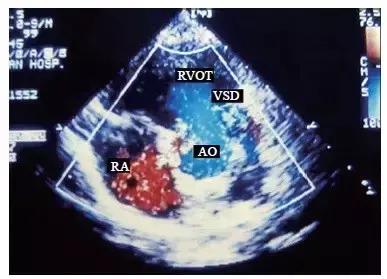

1.“主动脉骑跨征”是法洛四联症最具特征性的形态学改变,即在胸骨旁左心室长轴切面可见主动脉根部的前壁与室间隔回声连续性中断,呈一较大的缺损,而且缺损的两个残端不在同一水平,室间隔的残端在主动脉根部前后壁的中间。彩色多普勒血流显像显示收缩期有五彩镶嵌的血流由左心室和右心室同时射入粗大的主动脉,这是确诊主动脉骑跨的直接证据。

2.在大动脉水平短轴切面或左心室流出道水平短轴切面显示膜周部室间隔回声大部分缺失,由于室间隔缺损较大,其直径甚至可相当于主动脉根部的内径,故又可称之为非限制型室间隔缺损。彩色多普勒血流显像可以在此切面判断心内分流的方向:左向右分流时室水平过隔血流为红色,而右向左分流时则为蓝色。